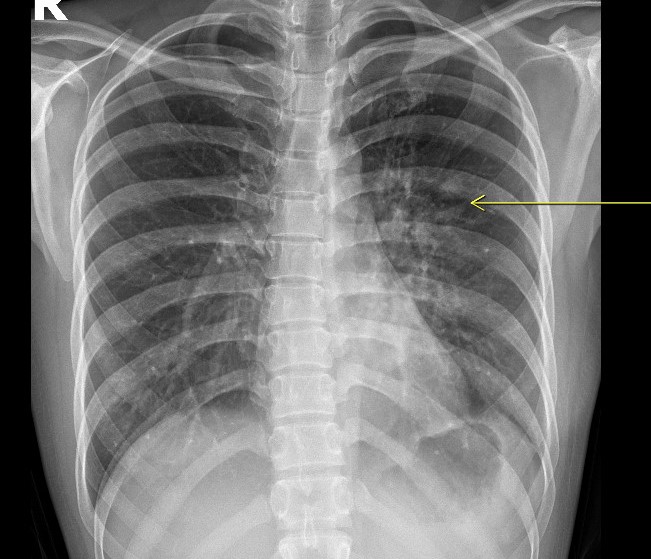

width= Hình ảnh chụp X-quang và phim chụp cắt lớp vi tính ở ngực bệnh nhân